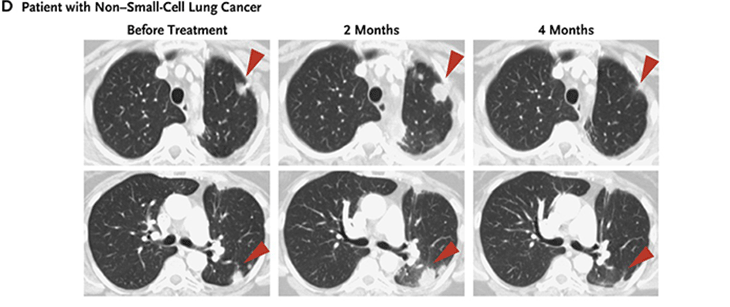

Now there are several antibodies against both PD-1 and its partner protein PD-L1. FDA has approved their use against melanoma, non-small cell lung cancer, kidney cancer, bladder cancer, head and neck cancers and Hodgkin lymphoma . Like the drugs that release the CTLA-4 brake, PD-1 antibodies have side effects. Still, they are generally milder than those due to the CTLA-4 brake release.